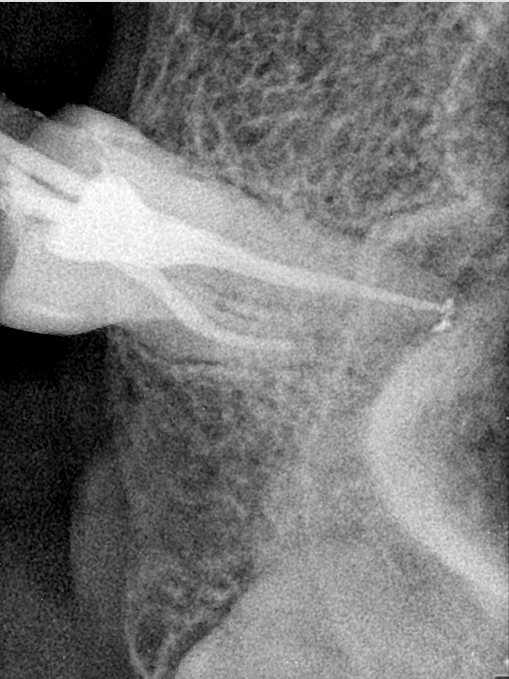

CR/DR 牙齿分割阶段记录

当前进展

- 完成了 CR/DR 牙齿相关分割训练

- 当前结果已经达到阶段预期,但仍有细节问题需要继续处理

相关测试

遇到的问题

- 训练过程中出现过 mask 下移问题

- 部分结果会出现 box 填充异常

- mask 边缘仍然有比较明显的锯齿感